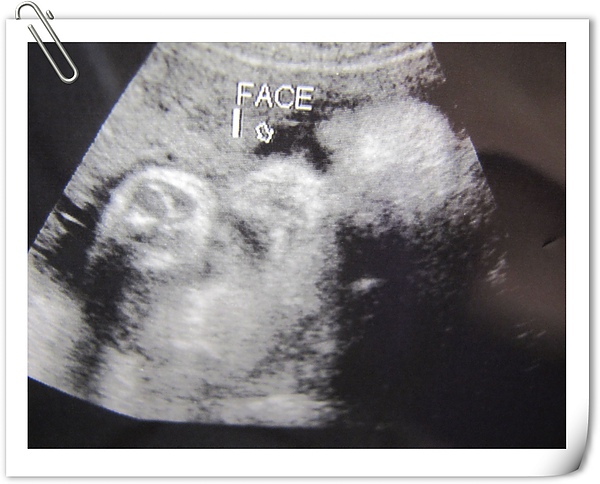

小臉,超音波師說他眼睛有張開一點點